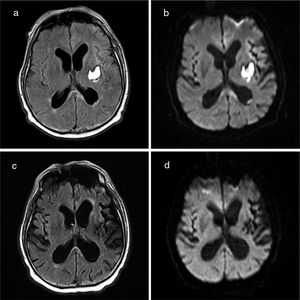

We present the case of a 66-year-old man with history of hypertension and frequent alcohol consumption (48 g/day). He was admitted to the neurology department due to left internal capsule haemorrhage (Intracerebral Hemorrhage Score of 1) manifesting with unilateral motor symptoms. He required labetalol perfusion due to a tendency to hypertension. After 24-48 hours, he developed confusion, psychomotor agitation, and hallucinations. An axial CT scan performed at this time showed no changes with respect to baseline images. He started treatment with tiaprizal 100 mg/8 hours. In the following days, the patient presented fever and a progressive decrease in the level of consciousness. A blood analysis revealed leukocytosis and high C-reactive protein levels. We suspected a respiratory tract infection secondary to bronchoaspiration, and started antibiotic therapy; the patient was transferred to the intensive care unit for ventilatory support. Chest radiography revealed increased density in the right lower lobe. Blood, saliva, and urine cultures yielded negative results. The neurological examination revealed a Glasgow Coma Scale score of 10 (eye 4, verbal 1, motor 5), with mutism, right hemianopsia (lack of menace response), and right hemiplegia. Inflammatory biochemical parameters normalised after 12 days with antibiotic therapy, but fever persisted. An immunological study including tests for tumour markers and serology tests for neurotropic viruses in the blood and CSF yielded negative results. Electroencephalography revealed no epileptiform activity. A brain MRI scan performed 20 days after onset of coma revealed a lesion to the splenium of the corpus callosum, showing restricted diffusion (Fig. 1), and signs of subarachnoid haemorrhage in the left convexity. Due to suspicion of MERS in the context of probable posterior reversible encephalopathy syndrome (PRES), the patient remained under close neurological and haemodynamic monitoring, showing systolic blood pressure values around 140-160 mm Hg. The patient’s level of consciousness progressively improved and visual disorders resolved, but motor deficits persisted. A follow-up MRI scan performed 35 days after the initial study revealed nearly complete resolution of the corpus callosum lesion (Fig. 1).

MERS constitutes the clinical and radiological manifestation of a large group of processes, including infection, autoimmune diseases, antiepileptic drug toxicity, metabolic disorders, trauma, and PRES.5–7 The pathophysiology of the syndrome remains poorly understood. The corpus callosum, and particularly the splenium, has a high density of cytokine receptors, glutamate, and toxins, which makes it more vulnerable to cytotoxic oedema than other brain regions.7 The characteristic MRI findings in MERS (corpus callosum lesions with restricted diffusion) have been interpreted as cytotoxic oedema,8,9 which may be caused by cytokinopathy.7